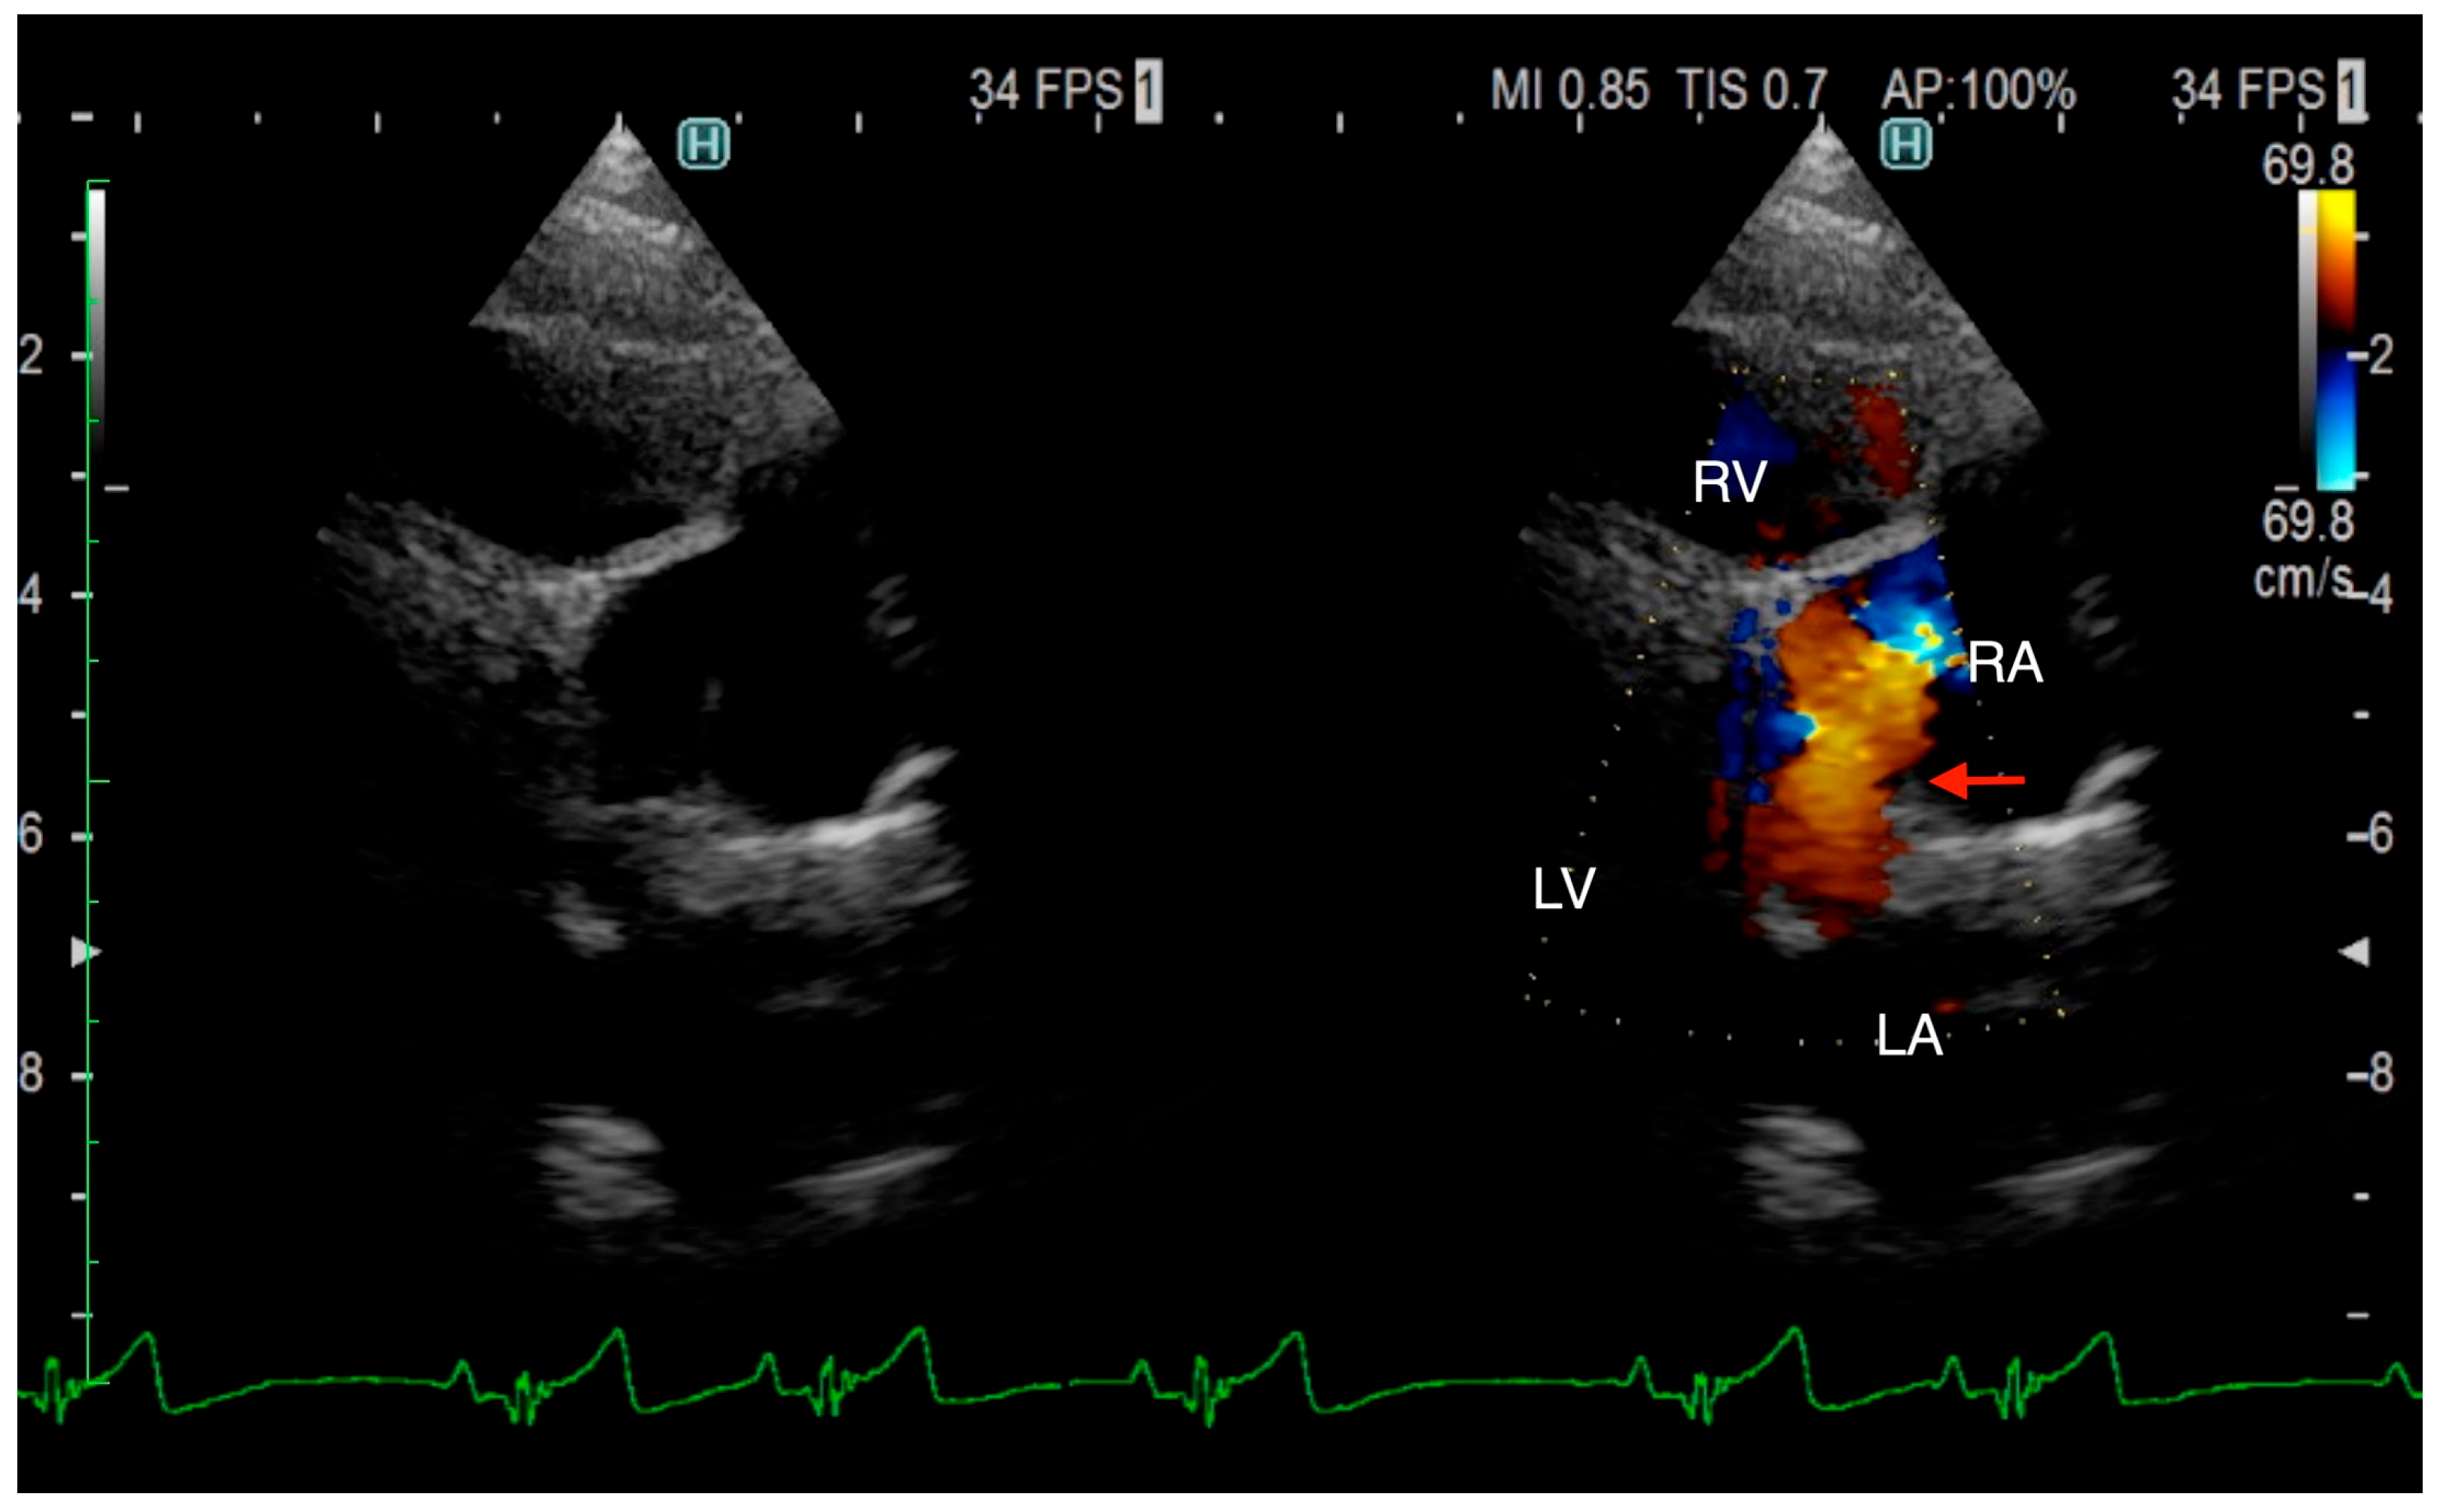

The ECG-gated CT showed communication between the LA and RA via the CS (Figure 2a). An enlargement of the CS, where the coronary artery measured 0.8 mm in diameter, whereas the CS measured 11.6 mm, was observed (Figure 2b). The CS drained normally into the RA; however, an ostium to the LA was seen, leading to the diagnosis of UCSS (Figure 3a). Under general anesthesia, TEE was also conducted using LISSENDO 880LE (Fujifilm Ltd., Tokyo, Japan) equipped with the 8–2 MHz phase array transesophageal probe (Fujifilm Ltd., Tokyo, Japan). With TEE, it was possible to identify the shunt as an abnormally large CS running along the cardiac wall (Figure 4).

A great supporting tool for the diagnosis of UCSS is TEE. In our patient, the blood flow from the CS to the RA was better visualized on the TEE than on the TTE. Shi et al. reported that out of all 159 human patients who had TEE performed, UCSS was confirmed in 91 cases (57.2%) [19]. TEE is widely recognized for its utility in diagnosing congenital heart diseases, including PDA [20].

Figure 4. Transesophageal echocardiography (TEE) shows the coronary sinus (CS) draining into the right atrium (RA) (arrow). The CS is typically not visible on TEE; however, in our patient, it is seen, suggesting that it is dilated due to an unroofed segment or an opening in the CS. CS, coronary sinus; RA, right atrium; AO, aorta; LA, left atrium.